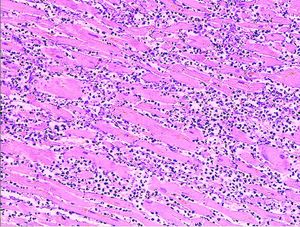

Histopathology

Microscopy image (magn. ca 100x, H&E stain) from autopsy specimen of myocardial infarct (7 days post-infarction).

Microscopy image of myocardial infarction scar in the heart of a rat